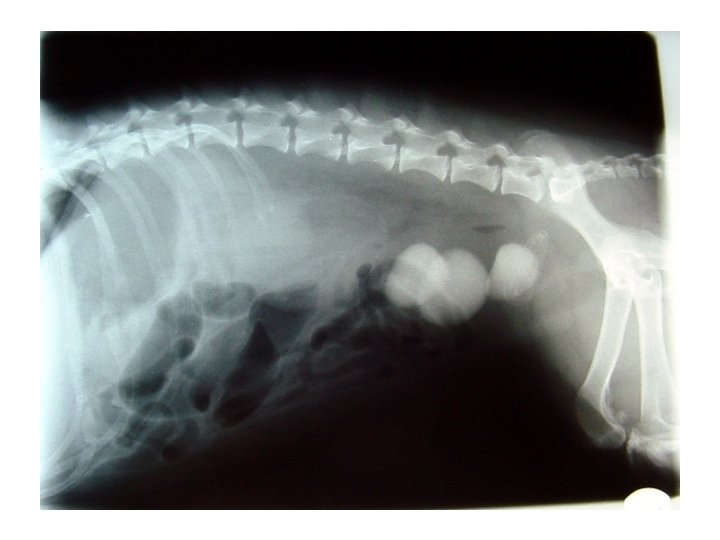

85% of canines with struvite stone occurrence occurs in females. Predisposed breeds include beagle, schnauzer and cocker spaniels. The average for stone occurrence is 2 ½ years.

Calcium oxalate stones can not be dissolved by diet and must be surgically removed. 50% of animals who undergo cystotomy sx will redevelop stones within 3 years.

Cystotomy :